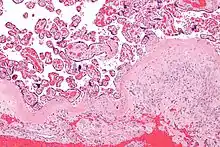

و الساقط لديه مظهر تشريحيا متميز، تظهر خلايا متعددة الأضلاع الساقطية كبيرة في سدى . هذه هي خلايا انسجة بطانة الرحم الموسع، التي تشبه ظهارة ( و يشار إليها باسم " شبيه الظهارة " ) . ويسمى تشكيل الساقط المتخصصة decidualization ، الذي هو صفه خاصة لبطانة الرحم يتم رؤيتها فقط في المشيمة الدموية "مشيمائية" .

عملية تكوين الساقط يشمل التفريق بين شكل المغزل في الخلايا الليفية انسجة الخلايا الإفرازية الساقطية، أي إنشاء المصفوفة خارج الخلية المحيطة بالخلايا الغنية في فبرونيكتين و laminin ( مماثلة ل خلايا الظهارية ) . الأوعية الدموية، وكذلك نفاذية الأوعية الدموية ، مما يعزز في بطانة الرحم الساقطيه. الكريات البيض سكانها متميز، مع وجود الكريات البيض بطانة الرحم الحبيبية كبيرة تكون غالبة، في حين أن الكريات البيض متعددة النوى وخلايا B هي سكانيا. وتسمى الخلايا الليمفاوية الحبيبية الكبيرة ( CD56 الساطع) " خلية الرحم NK " أو " الخلايا UNK " في الفئران، و " الخلايا القاتلة الطبيعية الساقطية " أو " الخلايا DNK " في البشر.منطقة تنكس فبريني حيث يتقابل الساقط و trophoblasts تدعي طبقة نيتابوخ . هذه الطبقة هي غائبة في ملتحم المشيمة .